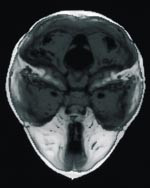

Cerebral CT med tredimensjonal rekonstruksjon viste lukket metopicasutur og trigonocefalistigmata (fig 2). For øvrig var det normalt store ventrikler og upåfallende intrakraniale forhold.

Cerebral CT med tredimensjonal rekonstruksjon viste lukket metopicasutur og trigonocefalistigmata. For øvrig var det normalt store ventrikler og upåfallende intrakraniale forhold.